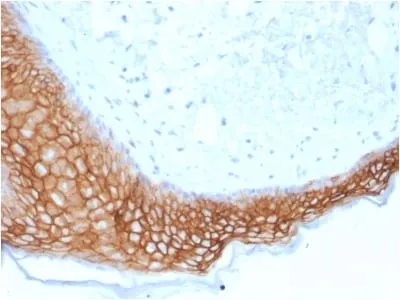

Anti-TACSTD2 / TROP2 (Epithelial Marker) (TACSTD2/2153), Biotin conjugate